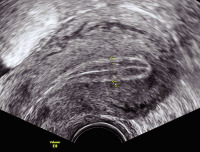

Tipps und Tricks im Gyn-Ultraschall: Das prämenstruelle und das menstruelle Endometrium

Journal für Gynäkologische Endokrinologie 2013; 7 (3) (Ausgabe für Österreich): 24-25 Journal für Gynäkologische Endokrinologie 2013; 7 (3) (Ausgabe für Schweiz): 33-34 Volltext (PDF) Abbildungen